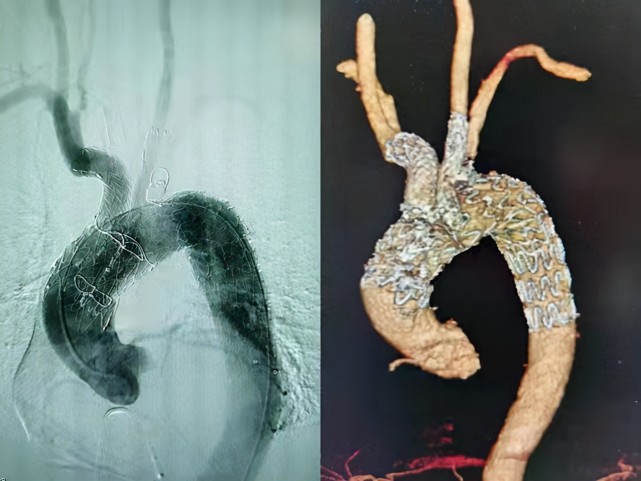

右椎a支架术后血管闭塞复合手术再通术 王东海 赵鹏 山东大学齐鲁医院

图片尺寸1076x614